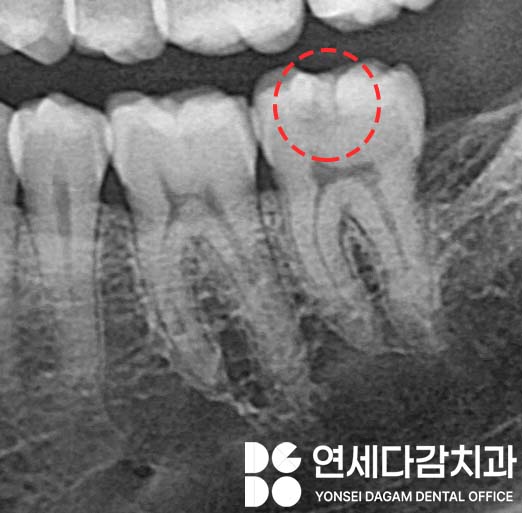

중기에는 상아질까지 진행된 상태로,

이때부터 본격적인 증상이

나타나기 시작합니다.

차가운 음식이나 단 음식에 시린 증상이 생기고,

육안으로도 눈에 띄기 시작합니다.

내부에 진행된 경우

가락동 치과 에서 표시한 것처럼

어둡게 비춰 보이곤 합니다.

이때부터는 적극적인

치료가 필요합니다.

상아질은 법랑질보다 구조가 연약해서,

충치가 빠르게 확산되는 특성이 있기 때문이죠.

치료는 인레이(inlay) 또는 큰 범위의

복합레진 충전으로 이루어집니다.

이때는 우식 발생 부위와

진행 정도를 파악하기 위한

엑스레이를 촬영해야 됩니다.

치수까지 감염이 진행되지는 않았는지

확인한 뒤 인레이 치료 범위를 파악합니다.